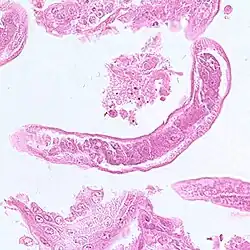

| Capillaria infectie bij een zestienjarig Filipijns meisje | ||||||||||||||

Volwassen mannetjes zijn 1,5-3,9 mm lang en 23-28 µm dik. De vrouwtjes zijn 2,3-5,3 mm lang en 29-47 µm dik. De eieren zijn 35-45 µm lang en 20-25 µm breed en hebben een gestreepte buitenwand.

Bacillaire band (blauwe pijl), darm (rode pijl) en uterus met een ei in dwarsdoorsnede (zwarte pijl)